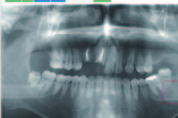

제품의 ‘지능화’를 특징으로 하고 있는 제4차 산업혁명의 흐름은 치과의 현장을 어떤 모습으로 바꿀까? 머지않은 미래의 단면을 엿볼 수 있는 장면 하나가 최근 한 치과대학병원에서 시연돼 참석자들의 큰 관심을 불러 모았다. # 6초 만에 병변 정확히 짚어내 지난 10일 분당서울대병원 헬스케어혁신파크. 치과용 X-레이 판독용 기계인 ‘자비스’가 X-레이 사진을 분석하더니 36, 37번 치아에 빨간색 동그라미를 표시한다. 시간은 대략 6초가 걸렸다. 이 환자의 진료한 담당의는 해당 사진에 “36, 37번 치아 아래에 치근낭종이 발견된다”고 결론 내린 바 있다. 자비스의 진단과 담당의의 진단이 일치하는 것이다. 치아 뿌리, 모세혈관, 함몰된 치아의 주변 등에 낭종이 생겼다고 진단받은 환자 20명의 X선 사진을 분석하는 실험에서도 자비스는 거짓사진 5종을 구별, 20장 중 총 18장의 병변을 정확하게 짚어냈다. 1장은 사진 상 얼룩으로 구별해 내기 어려운 상황이었고, 나머지 1장은 의사가 진단한 2가지 병명 가운데 1가지를 맞혔다. 사실상 100프로에 가까운 정확성이다. 자비스는 OBS코리아와 서울대치과병원이 공동개발하는 치과용 X선 판독기기로, 지난해 이세돌과 대국하